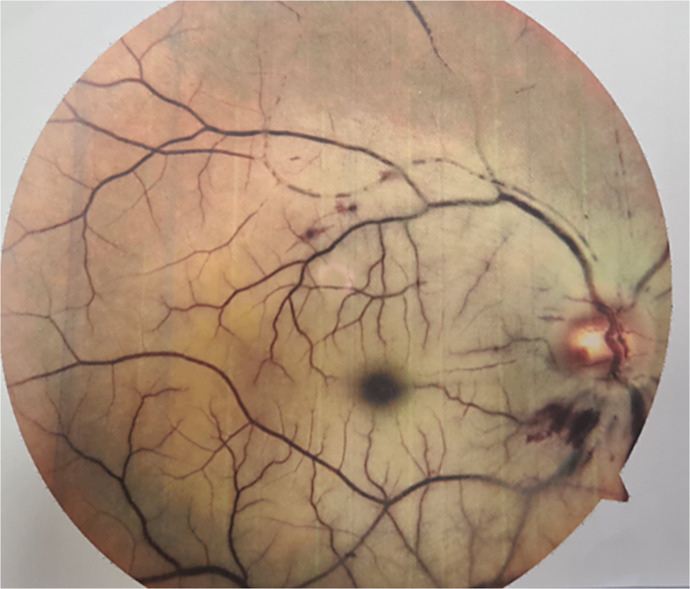

Case report: A 45-year-old woman presented with sudden vision loss in her right eye 3 h after sustaining blunt trauma from a wood fragment while chopping firewood. Initial examination revealed no light perception (NLP) in the affected eye and a relative afferent pupillary defect. Imaging revealed hyperdensity and thickening of the posterior sclera, the intraocular and anterior intraorbital optic nerve. Despite administration of intravenous steroids and a neurosurgical consultation for TON, retinal evaluation 1 day post-trauma revealed retinal edema, pallor, multiple vascular occlusions, and a cherry-red spot, leading to a diagnosis of CRAO associated with TON. Ongoing follow-ups showed persistent NLP in the right eye.